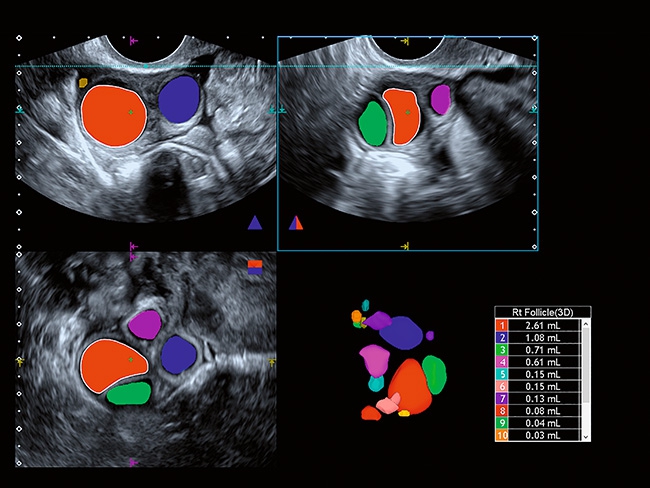

Отличная цветопередача с высокой детализацией и четкостью изображения. Устройство подходит для профессионального использования в частных кабинетах и крупных медицинских центрах. Комплектация сканера применима для самых разных исследований. Широкий диапазон прикладного клинического программного обеспечения высокоэффективен для общих исследований, сердечно-сосудистых, гинекологических, ортопедических, урологических.

Трехмерная реконструкция ЦДК:

Да

Гинекология: